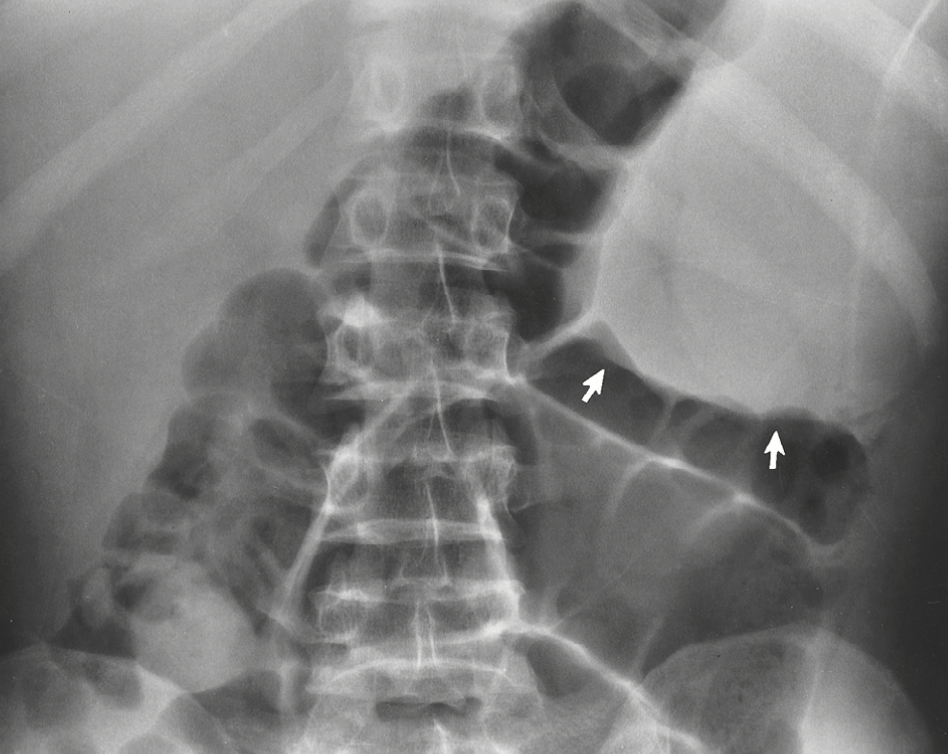

transverse radiolucent bands at the metaphyseal ends of long bones “moth-eaten”

leukemia radiographically

splenomegally

KUB with leukemia can also represent as:

Most common non-skeletal radiographic appearance